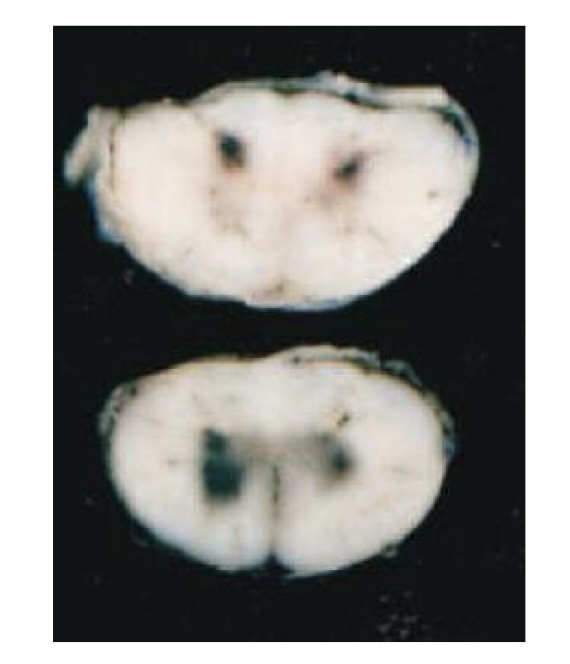

what is this?

medulloblastoma → white to tan, homogenous mass that compresses the cerebellum and brainstem